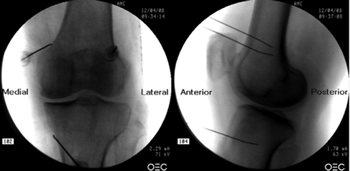

Fluoroscopy-guided genicular nerve radiofrequency

To perform a fluoroscopic-guided TRFGN, we need an anteroposterior (AP) and lateral view of the knee (Figure 2). First we place the patient in supine position with a pillow under the popliteal fossa (to make the patient more comfortable) (16). After performing asepsis and antisepsis of the knee, we proceed to locate the GN (Table II). SLGN is advancing the TFR needle toward the confluence of the lateral femoral diaphysis with the lateral femoral condyle in an AP view and at a mid-point of the femur in a lateral view. The SMGN is located by advancing the needle toward the confluence of the medial femoral diaphysis with the medial femoral condyle in an AP view and at a mid-point of the femur in a lateral view. Finally, the IMGN is located by advancing the needle toward the confluence of the medial tibial diaphysis with the tibial epicondyle in an AP view and at a midpoint of the tibia in a lateral view (16,17).

Fig. 2. Anteroposterior (AP) and lateral projection where therapeutic targets are observed using fluoroscopy. Image taken from Choi et al. (9). Reproduced with the permission of Jin Woo Shin.

Good AP and lateral view is very important. In AP projection, the tibiofemoral joint should have a similar width on both sides of the knee with the interspace open (9). In lateral projection, there must be a correct overlap of both femoral condyles to perform a satisfactory blockage of the SMGN and SLGN (18).

Most authors take the references described above to locate these nerves by fluoroscopy, except Fonkoué et al. (18), who find that the therapeutic targets of SMGN and SLGN (in a lateral view) are at the junction of the upper edge of their respective femoral condyles with the posterior cortex of the femur diaphysis, and not in half the thickness of the femur, as described classically (9,10,13).

Because the success of the TRF of the genicular nerves depends on the correct location of the RF needle tip (as close as possible to the nerve), Know et al. (17) demonstrated with magnetic resonance imaging that the points used classically in fluoroscopy for ablation of the three genicular nerves (SMGN, SLGN and IMGN) are correct. They observed that GN passes through the intersection formed by the diaphyseal and metaphysis line of the distal femur or proximal tibia (SLGN 92 %, SMGN 88 % and IMGN 100 %).